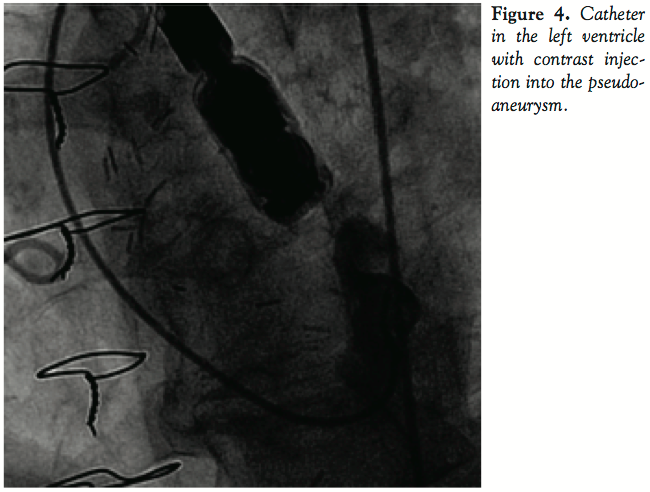

The patient was intubated and the procedure was performed under transesophageal echocardiography (TEE) guidance. The TEE showed a large LV pseudoaneurysm in the posterior aspect of the base of the left ventricle just below the mitral annulus. The neck of the aneurysm was 6 mm and the aneurysm size was 5.1 x 4.4 cm. A 7 Fr AL-2 guide catheter was used to engage the pseudoaneurysm (Figure 4) and a 0.035-in glidewire was advanced into it. A 5 Fr hypotube was advanced over the glidewire into the aneurysm cavity and

the glidewire was removed. Eighteen embolization coils of different lengths were advanced into the aneurysm cavity. The neck of the pseudoaneurysm was occluded using a 12 mm AGA Amplatzer II vascular plug. There was no communication between the LV cavity and pseudoaneurysm cavity after the plug was deployed (Figure 5).